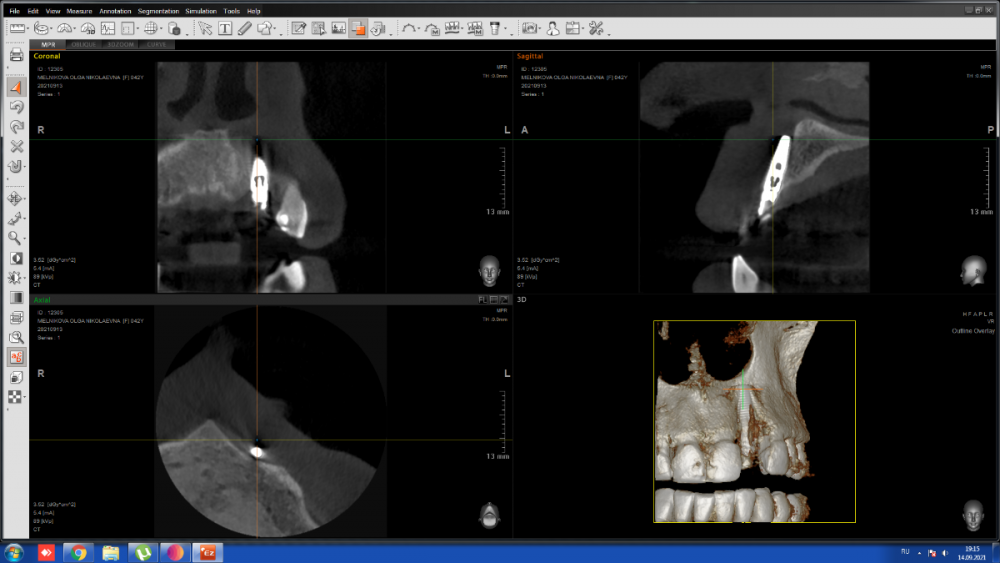

МОН Опубликовано 14 сентября, 2021 Автор Поделиться Опубликовано 14 сентября, 2021 Добрый вечер. Сделала вчера КТ зубов 21, 22, 23. Прилагаю часть срезов. Ссылка на комментарий

red_butler Опубликовано 15 сентября, 2021 Поделиться Опубликовано 15 сентября, 2021 2 минуты назад, МОН сказал: Интересно к чему я должна быть готова? к удалению импланта 1 2 Ссылка на комментарий

It'sGeorgy Опубликовано 15 сентября, 2021 Поделиться Опубликовано 15 сентября, 2021 Тему надо переименовать на «для чего делать КТ после имплантации и почему оптг в хирургии - бесполезная трата времени и денег» и показывать в ВУЗах. 1 Ссылка на комментарий

МОН Опубликовано 21 октября, 2021 Автор Поделиться Опубликовано 21 октября, 2021 Добрый день. Была недавно в клинике. Меня осматривал имплантолог и ортопед. Они посмотрели КТ, сказали, что по нему видно, как будто-то спереди импланта нет костной ткани. Проведя пальпацию пришли к выводу, что костная ткань прощупывается и имплан хорошо держится. Имплантолог сказал, что надо понаблюдать пол года. Подскажите, пожалуйста, что мне может грозить если имплант не будет удалён? Ссылка на комментарий